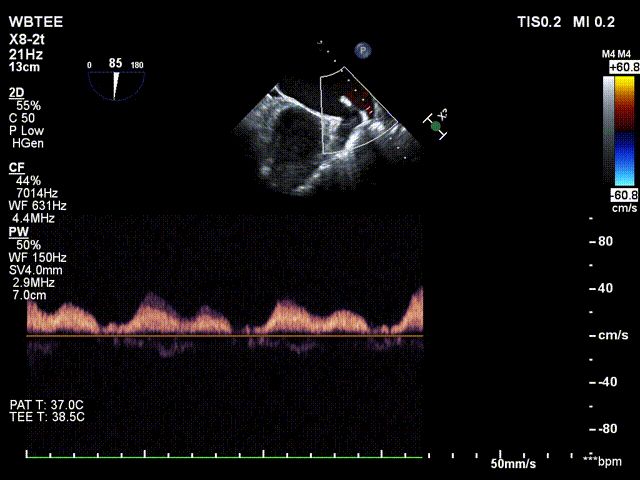

反复测试二尖瓣钳夹的稳定性,超声复查提示二尖瓣夹内侧反流有效改善,外侧仍有部分反流,平均跨瓣压差2mmHg,肺静脉收缩期逆流频谱恢复正向,傅国胜教授团队与超声影像团队充分沟通讨论,计划在二尖瓣夹外侧再置入第二枚二尖瓣夹,遂精准释放第一个二尖瓣夹。

傅国胜教授继续在食道超声影像引导下进行高难度操作,在第一个二尖瓣夹外侧再置入第二枚二尖瓣夹NTR。

再次反复测试第二枚二尖瓣钳夹的稳定性,超声复查提示二尖瓣反流明显改善,平均跨瓣压差4mmHg。